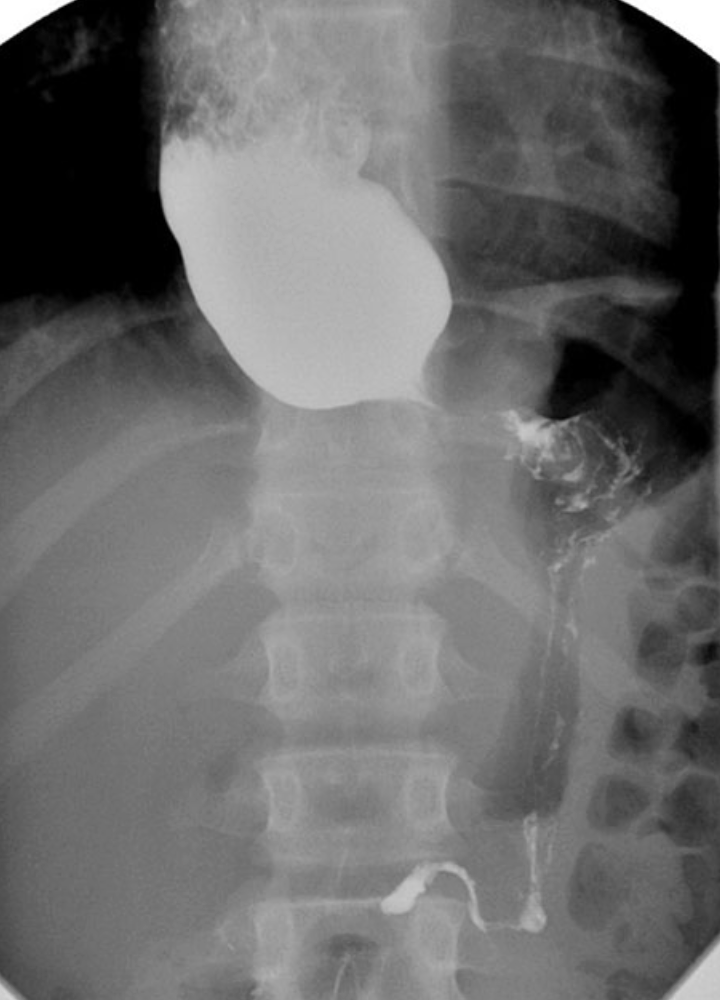

RA of achlasia

xray shows widened mediastinum with an air fluid level

radiographic signs include bird’s beak, string sign or corkscrew esophagus

bird’s beak sign of achalsia

narrowing along the length of the cardiac sphincter